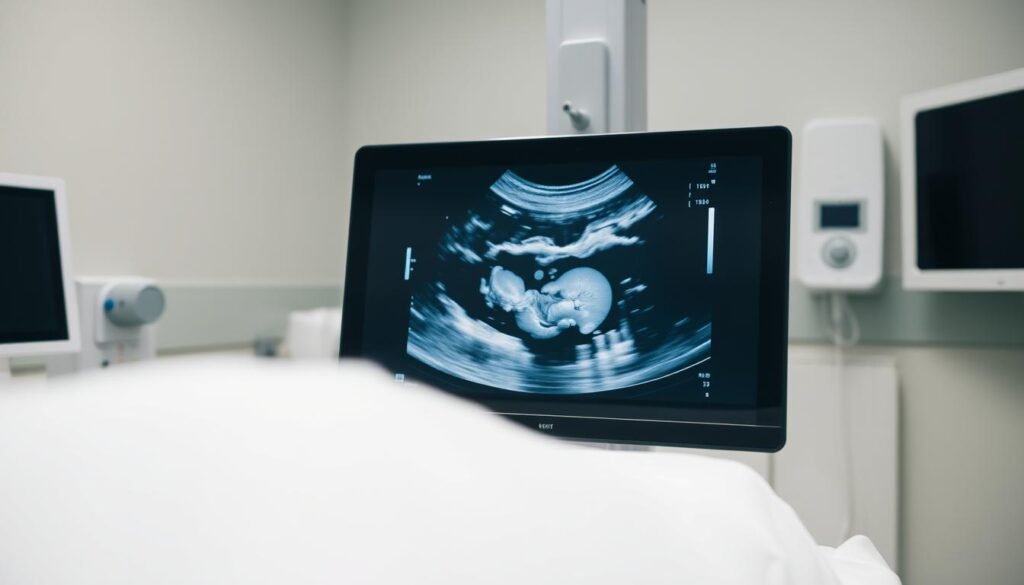

Échographie de grossesse

Permet de suivre le développement fœtal. 85% des Marocaines effectuent trois examens obligatoires durant leur grossesse.